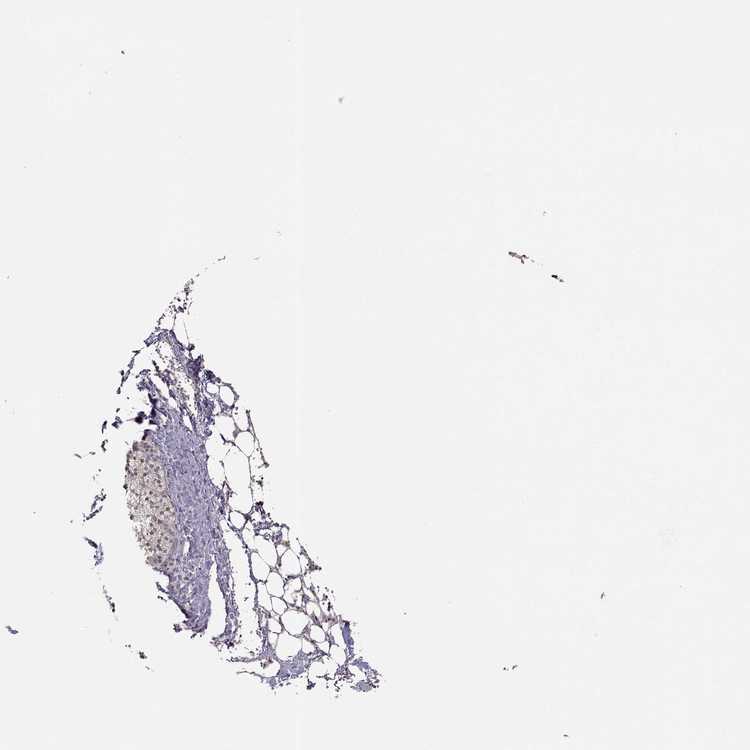

ADRENAL GLAND - Antibody stainingi

Antibody staining in the annotated cell types in the current human tissue is reported as not detected, low, medium, or high, based on conventional immunohistochemistry profiling in selected tissues. This score is based on the combination of the staining intensity and fraction of stained cells.

Each image is clickable and will lead to virtual microscopy that enables deeper exploration of all samples and also displays staining intensity scores, fraction scores and subcellular localization as well as patient and tissue information for each sample.

Antibody HPA004810Antibody CAB017615

Glandular cells Not detectedNot detected